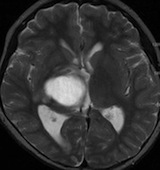

14歳少年の右視床中脳の毛様細胞性星細胞腫です

放射線治療前

生検術の後で48.6グレイ(1回線量 1.8グレイ,27分割)の放射線治療をしました。軽い左片麻痺がありました。テモゾロマイドを併用しています。

pseudoprogression スード・プログレッション

放射線治療の4ヶ月後くらいから腫瘍が大きくなりはじめ,麻痺が悪化しました。画像は放射線治療9ヶ月後のものです。腫瘍は大きくなって,周囲の脳浮腫が悪化して,閉塞性水頭症になっています。この間,大量のリンデロンを使いましたので,ステロイド治療の副作用で肥満になりました。この例のような,のう胞性拡大のようにみえるスードプログレッションは毛様細胞性星細胞腫の放射線治療後に特徴的に生じるものです。